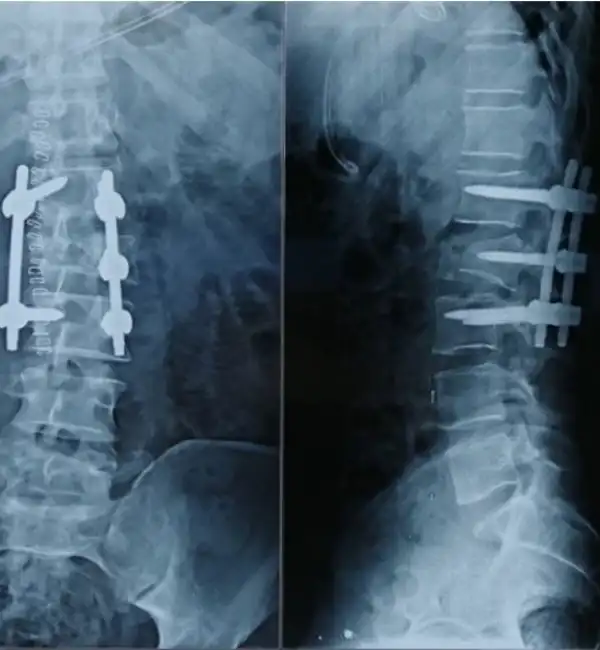

T2 Fracture Post Op

C6-7 Fracture dislocation Post op X ray

T7 fracture Post Op